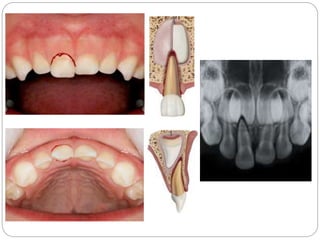

Primary teeth: Intrusion

Diagnostic signs

 Radiographs recommended:

 An occlusal or periapical exposure

 If the tooth is totally intruded an extra-oral lateral

exposure may be indicated to make sure that the

tooth has not penetrated the nasal cavity